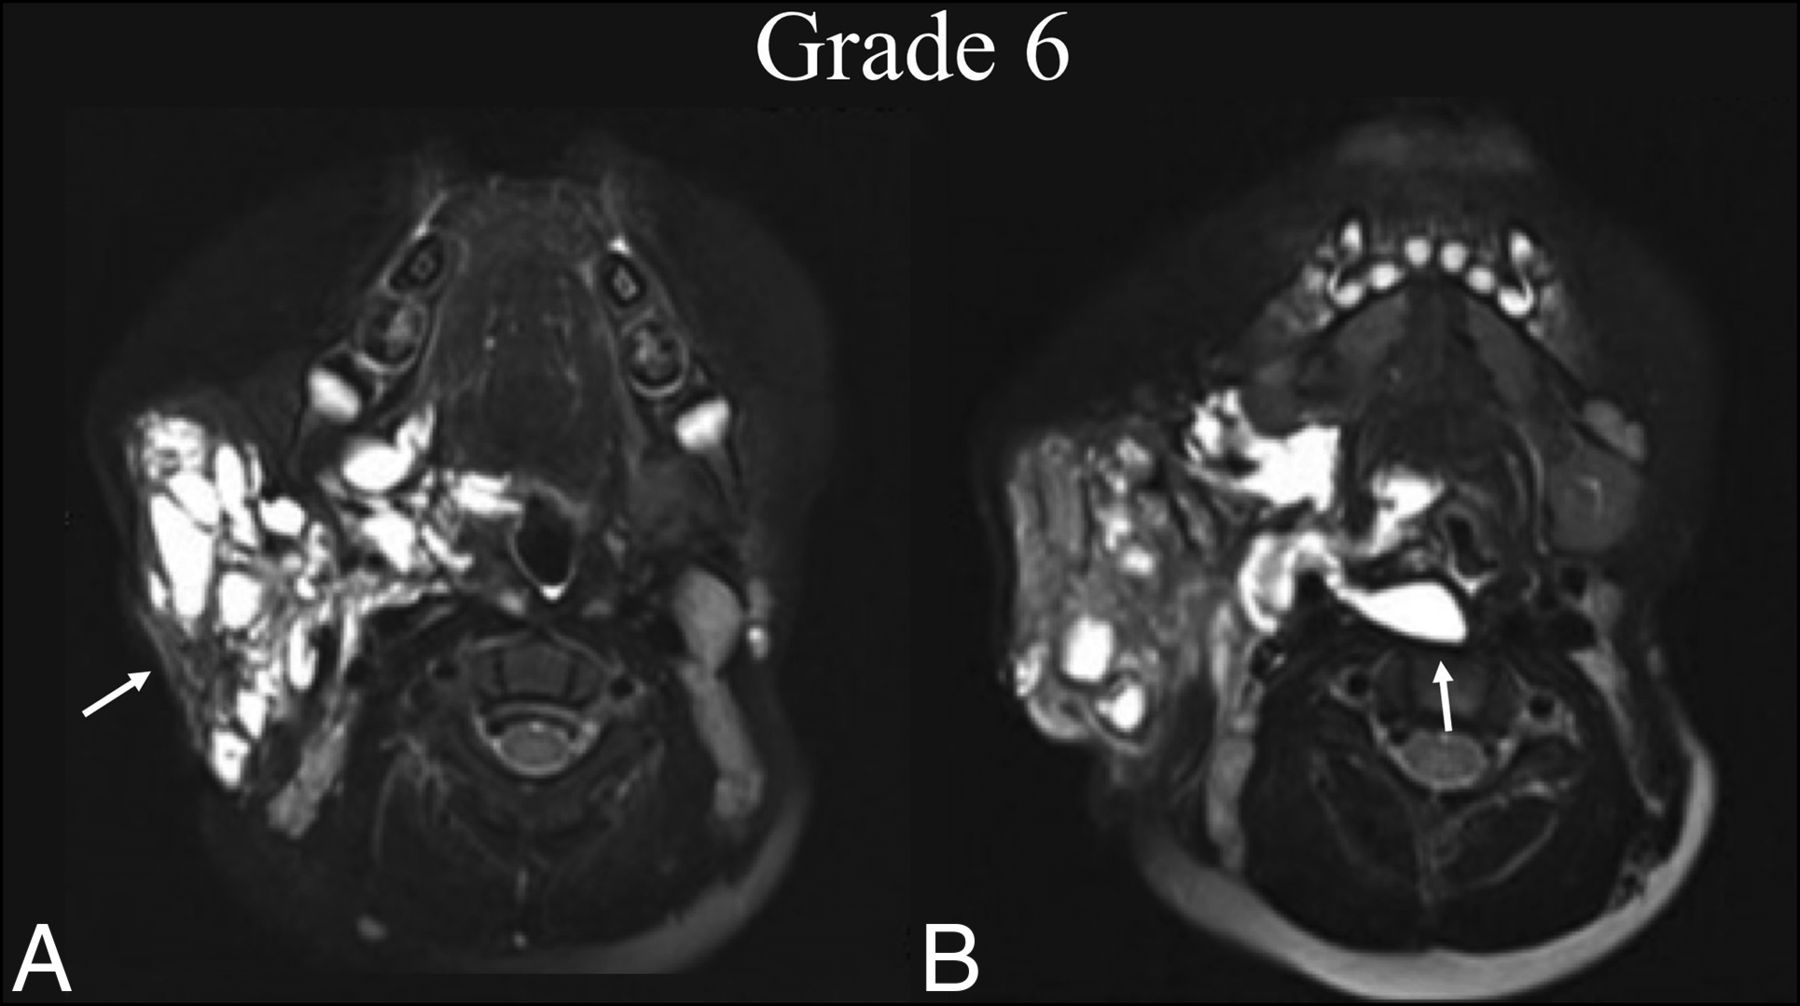

The 7-grade scale proposed and evaluated here stratifies radiographic improvement across 4 levels, illustrated by case examples in Figs 1–4. These grades include the following: 1) complete regression of the lesion, 2) near-complete repression with trace residual lesion, 3) partial regression with <50% residual lesion, and 4) partial regression with >50% residual lesion. Grade 5 indicates minimal or no interval change in the treated LM-LVM (Fig 5). Regression of the LM-LVM in 1 area, with expansion into a previously uninvolved area is denoted by grade 6 (Fig 6). Finally, gross interval progression is denoted by grade 7 (Fig 7). The formation of granulation tissue within the treatment bed, which may occur in conjunction with any radiographic grade, is indicated by the modifier B as illustrated in Fig 3. This modifier was omitted from analysis to preserve the statistical power of interrater testing; thus, its interrater reliability has not been evaluated. Nonetheless, it is included as a possible addition to each grade due to the clinical importance of granuloma formation, which is pathologically distinct from the LVM itself and may impede the improvement of cosmetic deficits or mass-related symptoms.

BDL grade 6 response. An 8-year-old boy with right facial prominence was found to have a de Serres stage II mixed macro-/microcystic LM. A, Preprocedural T2 fat-suppressed axial MR imaging at the level of the oropharynx shows trans-spatial involvement of the right neck extending from the right parotid and masticator spaces to the pharyngeal mucosal space (white arrow), sparing the retropharyngeal space. B, One year later, following 2 sclerotherapy treatments, T2 fat-suppressed axial MR imaging at the same level shows BDL grade 6 regression within the treatment bed and extension into the retropharyngeal space, which was previously uninvolved (white arrow).